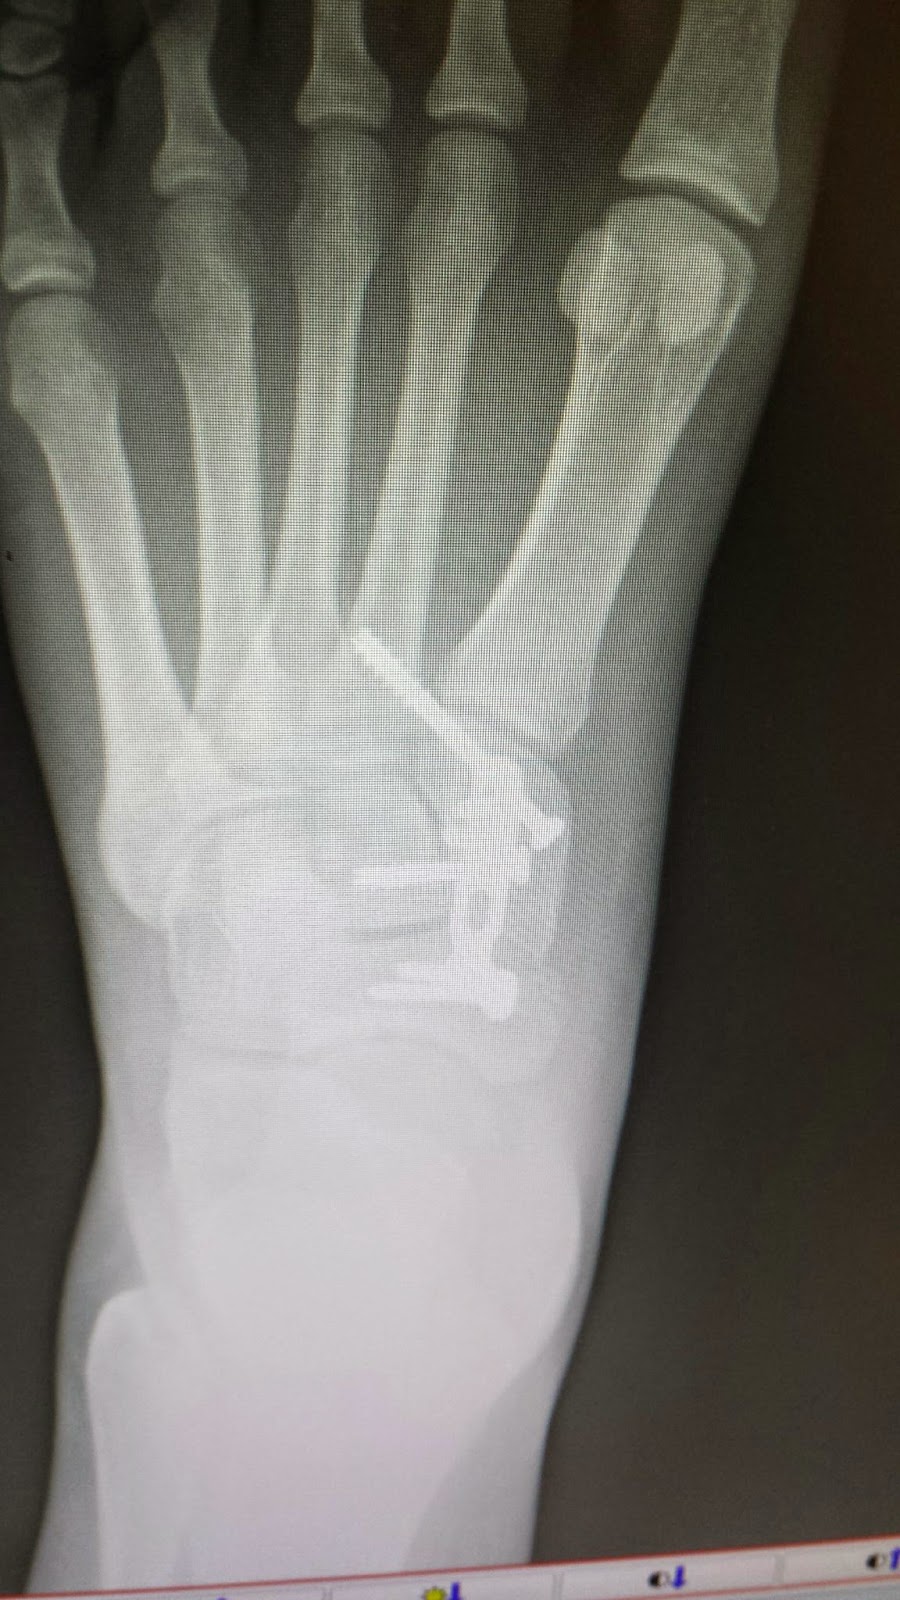

Crutching into Mayo on Friday morning everything finally felt real. Up until this point there was still a part of me that did not believe that all of this was happening to me. I was going to be fine and playing next week, not next year. As the doctors circled around me, attaching monitors, injecting medication, and setting up my IV I closed my eyes and thought of why I was going through all of this, to do what I love again. It is all going to be worth it when I am able to play again. After hugging my mom and telling her I loved her my wait was finally up.